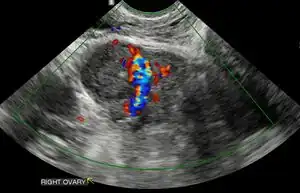

Ultrasound

Obstetric ultrasonography may also be used to detect and diagnose pregnancy. It is very common to have a positive at home urine pregnancy test before an ultrasound. Both abdominal and vaginal ultrasound may be used, but vaginal ultrasound allows for earlier visualization of the pregnancy. With obstetric ultrasonography the gestational sac (intrauterine fluid collection) can be visualized at 4.5 to 5 weeks gestation, the yolk sac at 5 to 6 weeks gestation, and fetal pole at 5.5 to 6 weeks gestation. Ultrasound is used to diagnose multiple gestation.[3][19]

Ultrasound is also a common tool for determining viability and location of a pregnancy. Serial ultrasound may be used to identify non-viable pregnancies, as pregnancies that do not grow in size or develop expected structural findings on repeated ultrasounds over a 1-2 week interval may be identified as abnormal.[34] Occasionally, a single ultrasound may be used to identify a pregnancy as non-viable; for example, an embryo that is greater than a certain size but that lacks a visible heart beat may be confidently determined to be not viable without the need for follow up ultrasound for confirmation.[34]